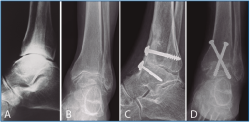

La segunda artrodesis se llevó a cabo durante el año siguiente a la primera intervención. La artrodesis fue tibioastragalina bilateral en 2 pacientes y tibiotalocalcánea (TTC) bilateral en el paciente restante. La estabilización ósea se realizó en un caso con 2 tornillos canulados Acutrak Plus® (Acumed, Hillsboro, EE. UU.) cruzados en ambos tobillos (Figura 1), en otro caso con clavo endomedular retrógrado T2 12 × 200 mm (Stryker, Schönkirchen, Alemania) en ambos tobillos (Figura 2) y en el último caso se utilizaron tornillos canulados Acutrak Plus® cruzados en el tobillo izquierdo y la técnica Putti en el tobillo derecho (Figura 3). La fijación de la artrodesis se realizó con el pie en plantígrado.

Figura 1. Caso 1. Varón de 47 años con artrosis primaria de tobillo bilateral. Corte coronal de tomografía axial computarizada (TAC) del tobillo derecho (A) e izquierdo (B) preoperatorio. Radiografía anteroposterior de artrodesis tibioastragalina con 2 tornillos canulados cruzados en tobillo derecho (C) e izquierdo (D) al año de la última intervención (tobillo derecho).